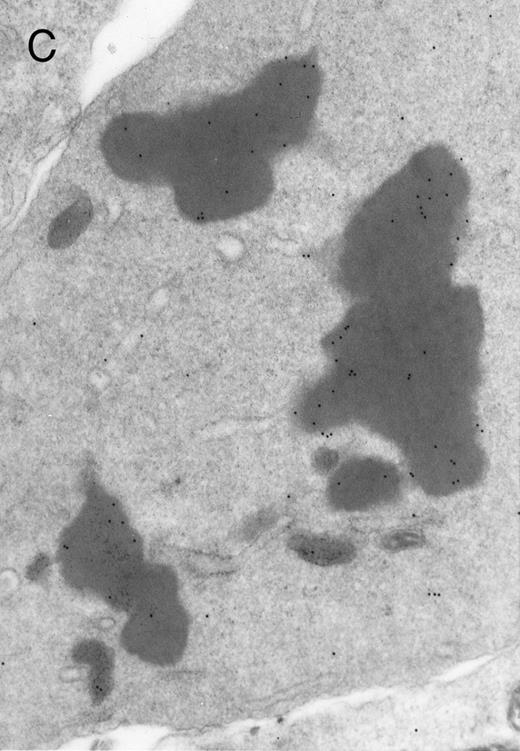

In both cases no. 1 and no. 2, electron microscope studies demonstrated electron-dense inclusions in 30% of early and late polychromatic erythroblast sections and many marrow reticulocytes. In ultrathin sections that reacted with monoclonal antibodies to either α- or β-globin chains followed by gold-labeled anti-mouse IgG, the density of gold particles over the majority of the inclusions was clearly greater than that over surrounding inclusion-free cytoplasm (Fig 3). By contrast, in sections from the two patients with β-thalassemia major, gold particles were concentrated over the inclusions following incubation with the antibody to α-globin chains, but not to β-globin chains (Fig 4A-C). The density of gold particles over inclusions in all control preparations was not greater than that over surrounding cytoplasm (Fig 4D).

Electron micrographs of erythroblastic inclusions from sections of marrow immunogold-labeled with mouse monoclonal antibody. Inclusions from case no. 1 show positive reactions with antibody against α-globin chains (A) and β-globin chains (B). Inclusions from case no. 2 show positive reactions with antibody against α-globin chains (C) and β-globin chains (D). Magnifications: A, × 32,000; B, × 38,000; C, × 32,000; D, × 37,000.